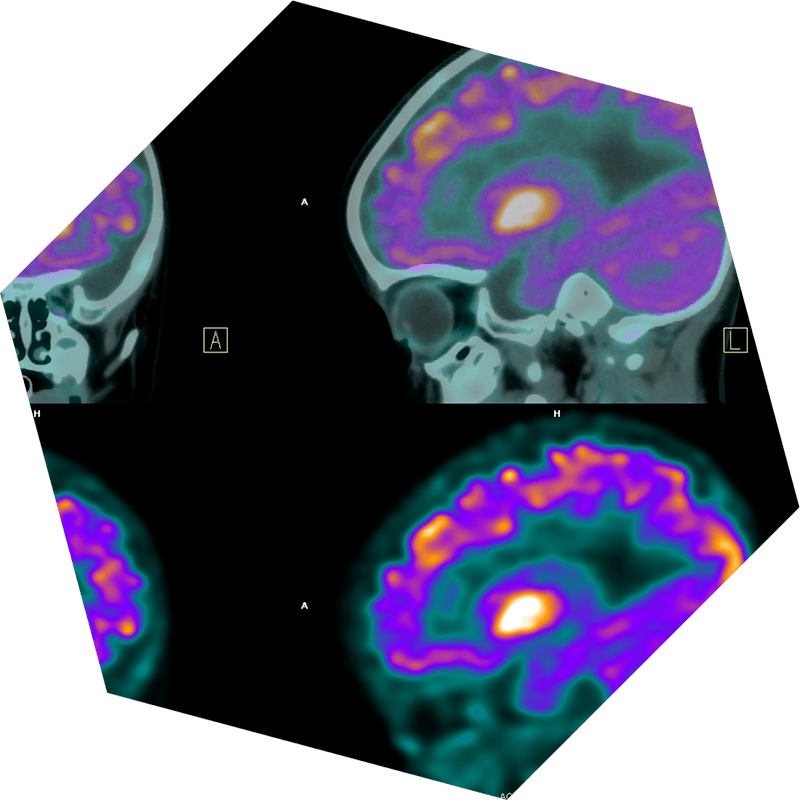

Tomografía Por Emisión De Positrones (TEP)

Las tomografías por emisión de positrones (TEP) revelan el nivel de actividad de los tejidos utilizando una cantidad pequeña de material radiactivo. Estas exploraciones detectan los rayos gamma emitidos cuando este material interactúa con las células. En la obtención de imágenes de los tumores cerebrales, las exploraciones por TEP ayudan a distinguir las células tumorales activas de las sanas debido al mayor metabolismo de las células del cáncer. Esto facilita el diagnóstico de los tumores agresivos, el seguimiento de su diseminación, el control de los efectos del tratamiento y la planificación de estrategias de tratamiento. Cuando se usan con otros métodos de diagnóstico por imágenes, las exploraciones por TEP ofrecen perspectivas esenciales para comprender y tratar los tumores cerebrales. En los casos de metástasis cerebrales de cáncer de otros órganos, o en la estadificación de linfoma del SNC, el médico podría indicar una exploración por TEP del cuerpo.